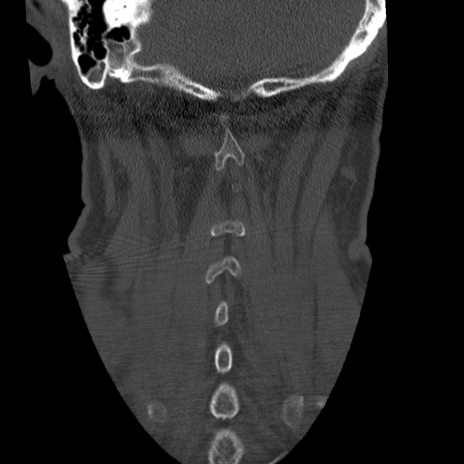

症例50 頚椎CT(冠状断像)

【症例】60歳代女性

【主訴】後頭部〜右後頸部にかけての痛み

【現病歴】本日飲食店でコーヒーを飲んでいたところ、突然後頭部〜右後頸部にかけて痛みが出現し、右上肢の感覚障害を伴ったため救急要請。

【身体所見】脳神経学的に明らかな異常所見を認めず。右上肢に軽度の感覚障害あり。

異常所見と診断は?